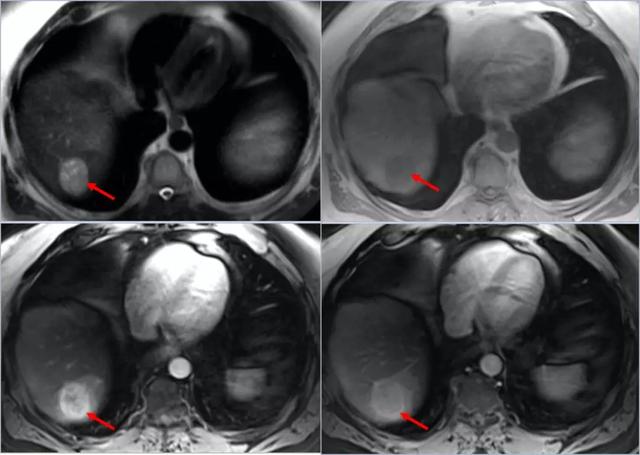

2014年核磁共振提示左肝占位,考虑肝癌.

其它 肝癌术后复查,再次tace 写美篇2019年5月肝脏肿瘤mri,和前一个

术前磁共振

肝细胞肝癌磁共振表现有哪些

肝脏mri 增强(t1 )